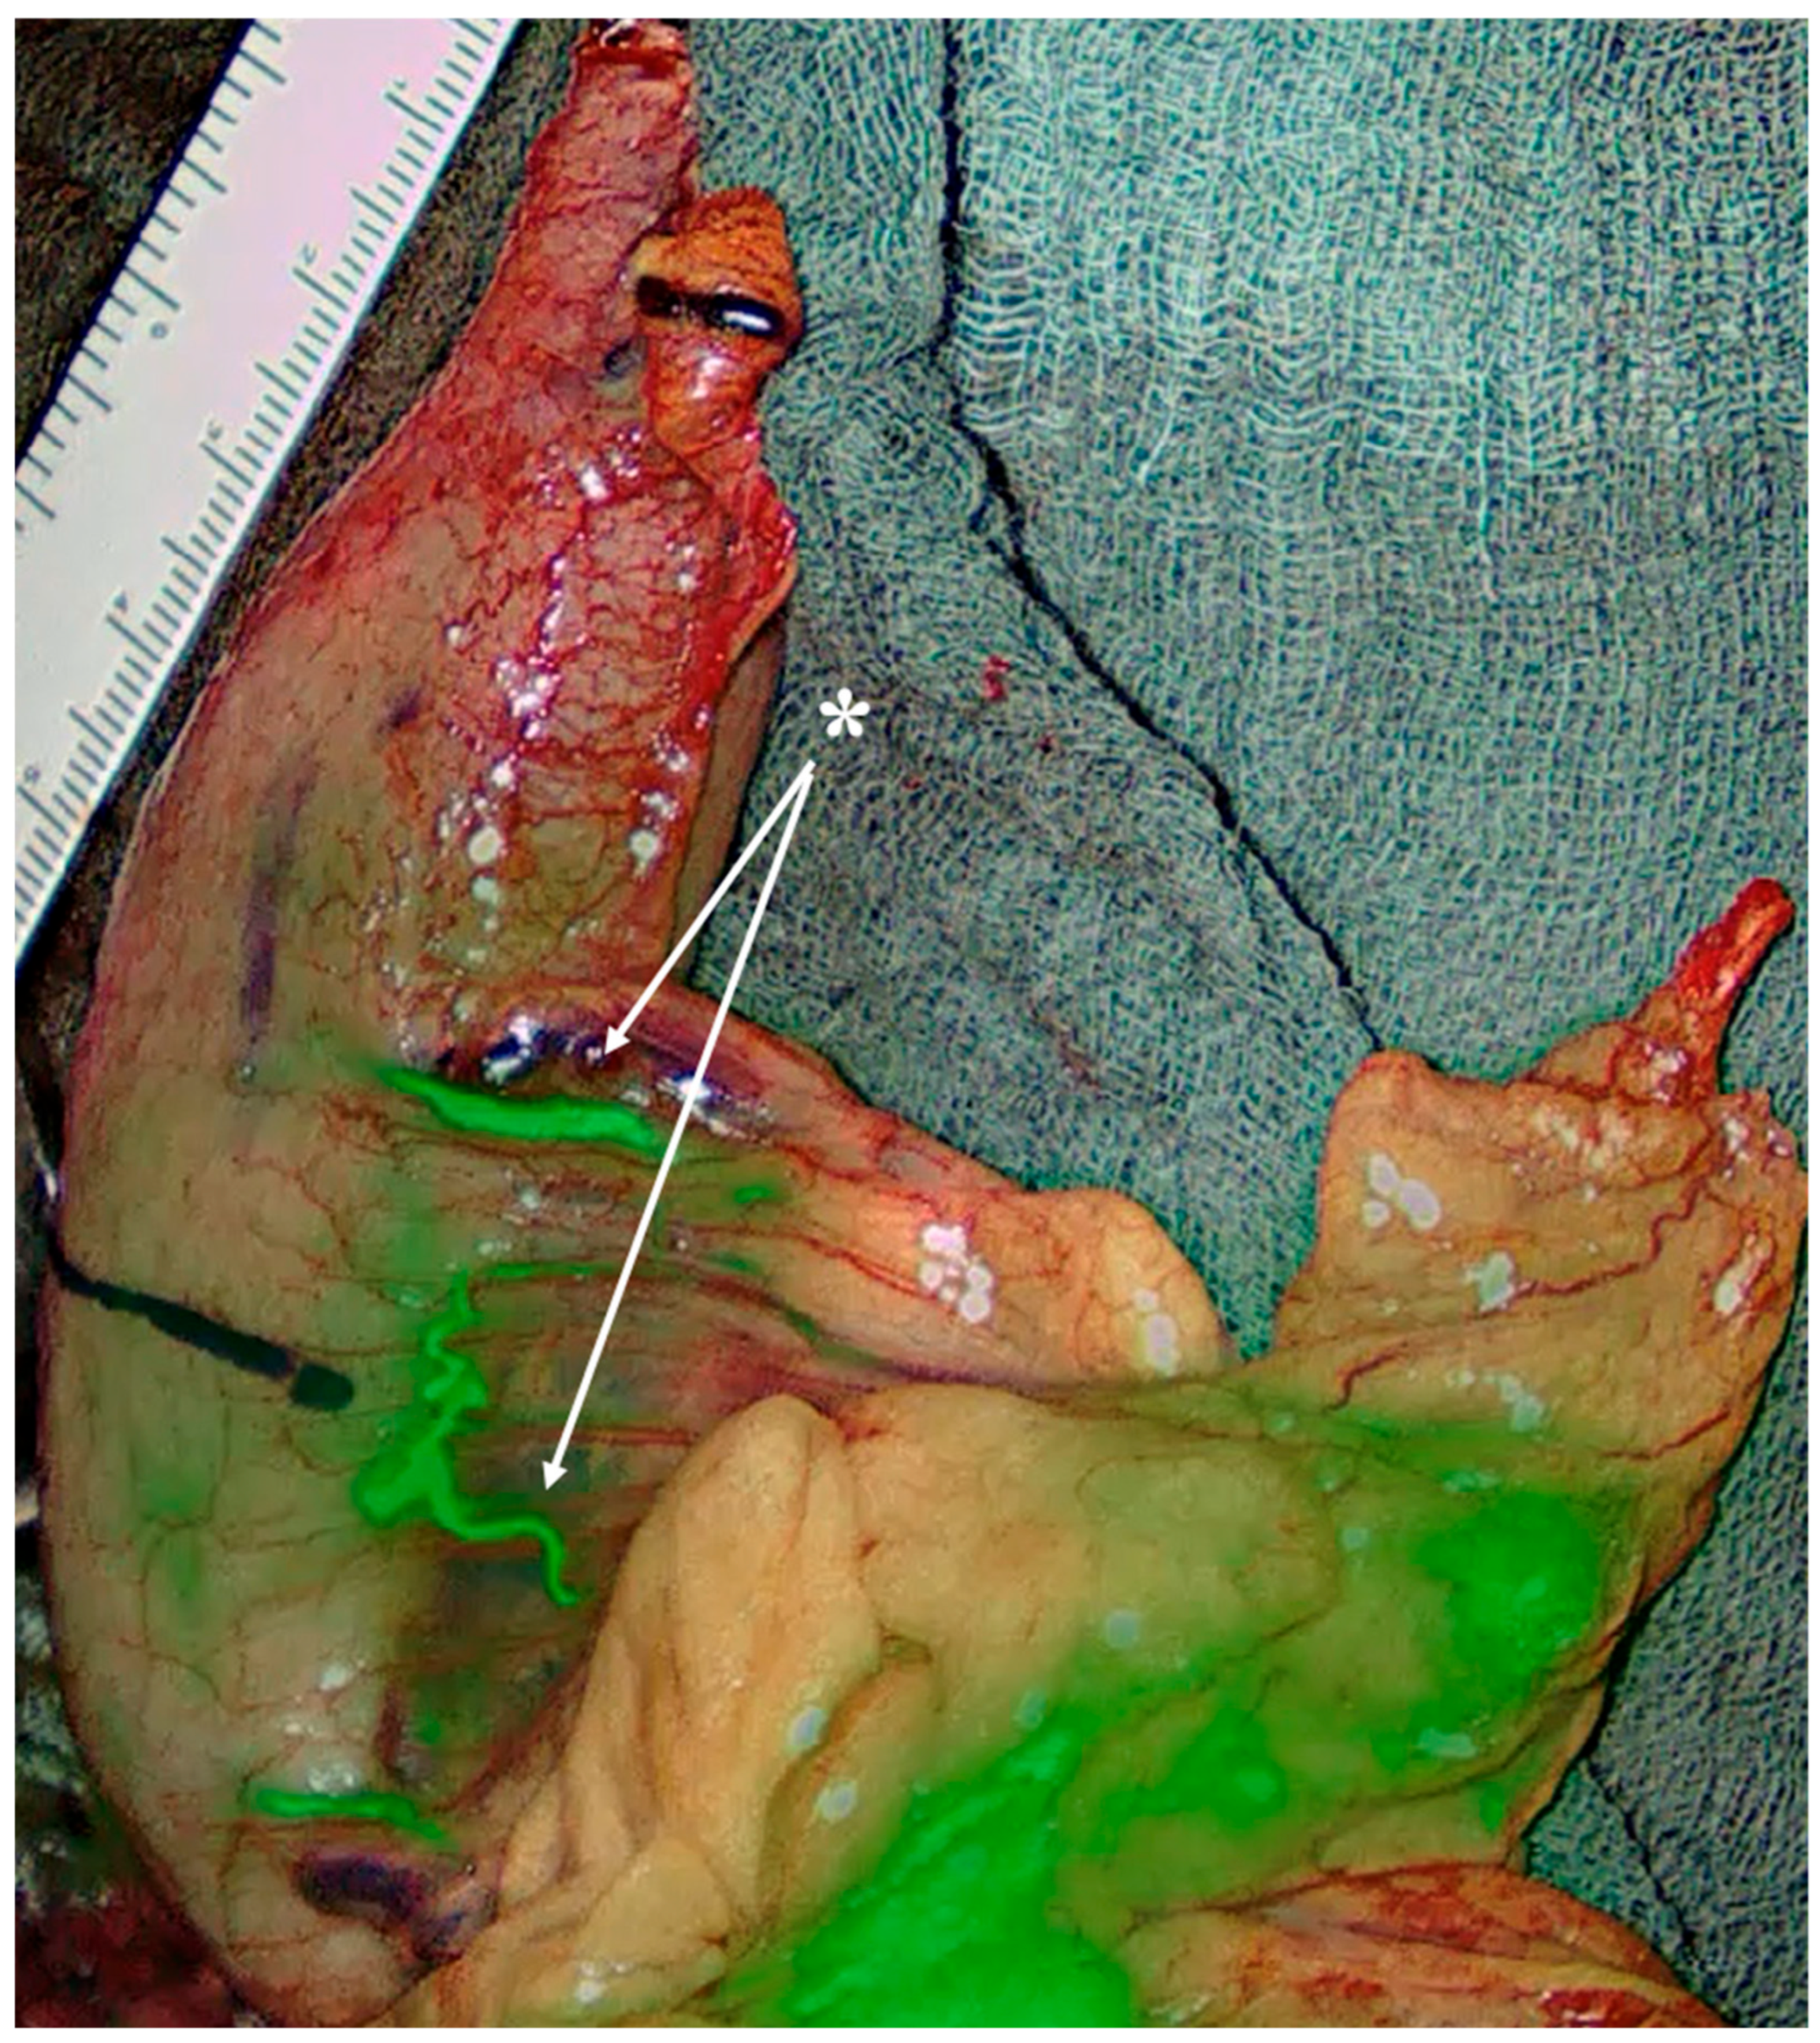

- Special consideration for PGA presence (approximately 57%): it represents a major inflow to the planned gastric remnant. Lymphatics course along the PGA, but D2 lymphadenectomy does not necessitate PGA division if nodal clearance can be performed while preserving arterial inflow. Preoperative MDCT can easily detect the PGA, while inadvertent ligation has been linked to stump ischemia/leak—use selective preservation and, if divided, confirm stump perfusion intraoperatively [27,28] (Figure 6).